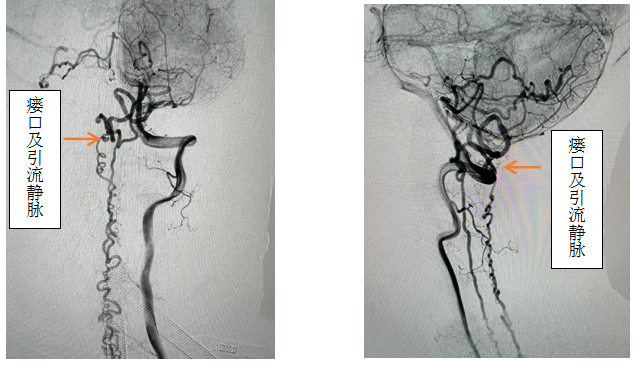

先进的复合手术室,首先采用第一方案“高压锅”技术使胶完全封堵瘘口,若不能到位或完全封堵,则采用第二方案,转为开颅阻断瘘口。手术当日,由黄卫东主任医师和李帅主治医师操作,第一根栓塞微导管顺利到达瘘口,第二根微导管接近栓塞微导管后使用弹簧圈顺利形成高压锅塞子,经第一根微导管注入栓塞胶,射线透视下见栓塞胶按预期流向瘘口,栓塞满意后造影示瘘口及引流静脉均未见显影,手术成功。术后患者恢复良好,第二天即下床活动,下肢活动明显恢复,5天后步行出院。